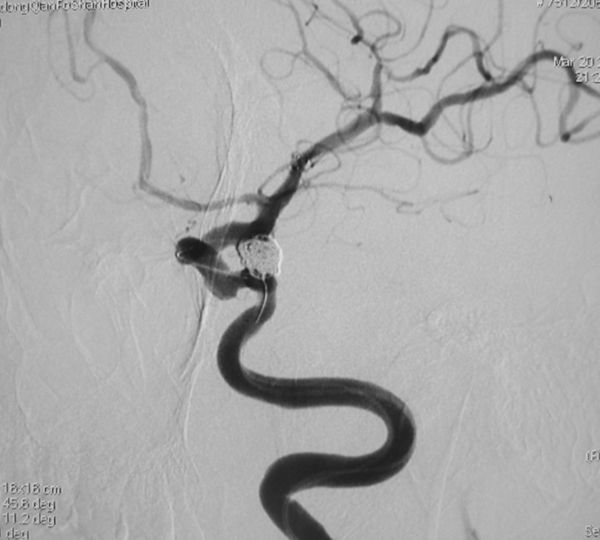

病例4、手术和栓塞均可以的动脉瘤:女性,58岁。右侧前交通动脉瘤破裂出血,动脉瘤大小3X3X2mm,患者已经是第二次出血,为防止动脉瘤再次破裂危及生命,需尽快处理动脉瘤。根据患者情况,手术夹闭和介入栓塞均可以,孟祥靖主任仔细向患者家属交代病情,并详细介绍了两种治疗方法的优缺点,家属经过慎重考虑,决定施行动脉瘤介入栓塞术。3月31日,孟祥靖主任带领郭建主治医师在介入科、麻醉科的密切配合下,顺利闭塞动脉瘤。患者恢复良好,已痊愈出院。

病例4:右侧前交通动脉瘤栓塞前后,以及显示弹簧圈